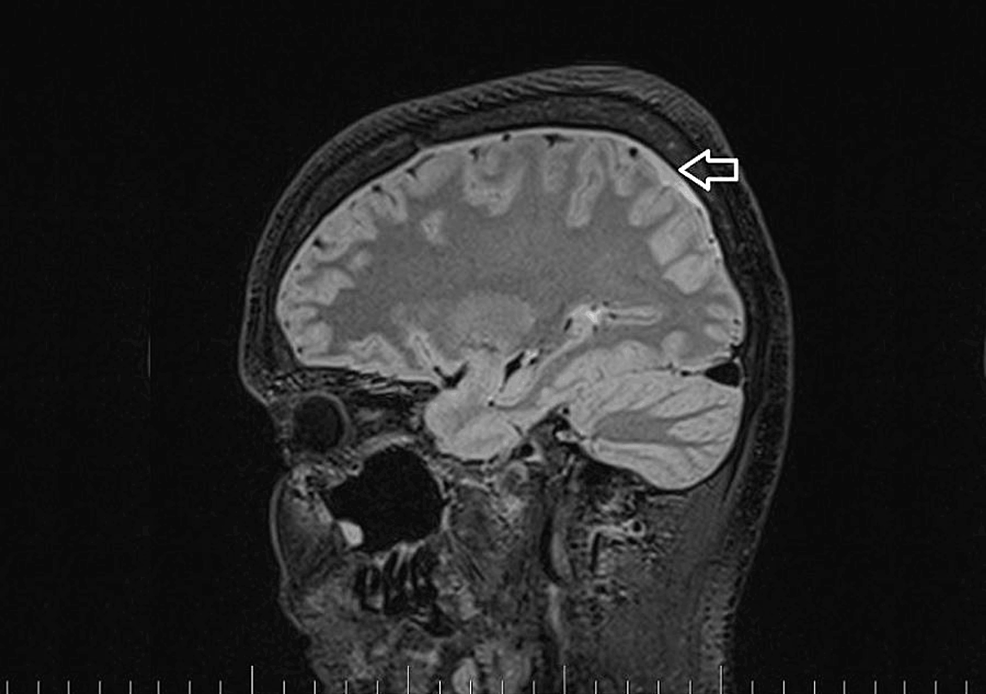

A brain and C spine MRI scan on March 5, 2023 (one month after the procedure) showed a regression of the subdural collection from 5.00 mm to 2.5 mm in the parietal area but all other parameters remained unchanged (Figure 3).

MRI myelography (Figure 4) showed no CSF leak. The SLEC was almost totally absorbed and only a tiny residuum persisted. The patient reported significant headache relief.